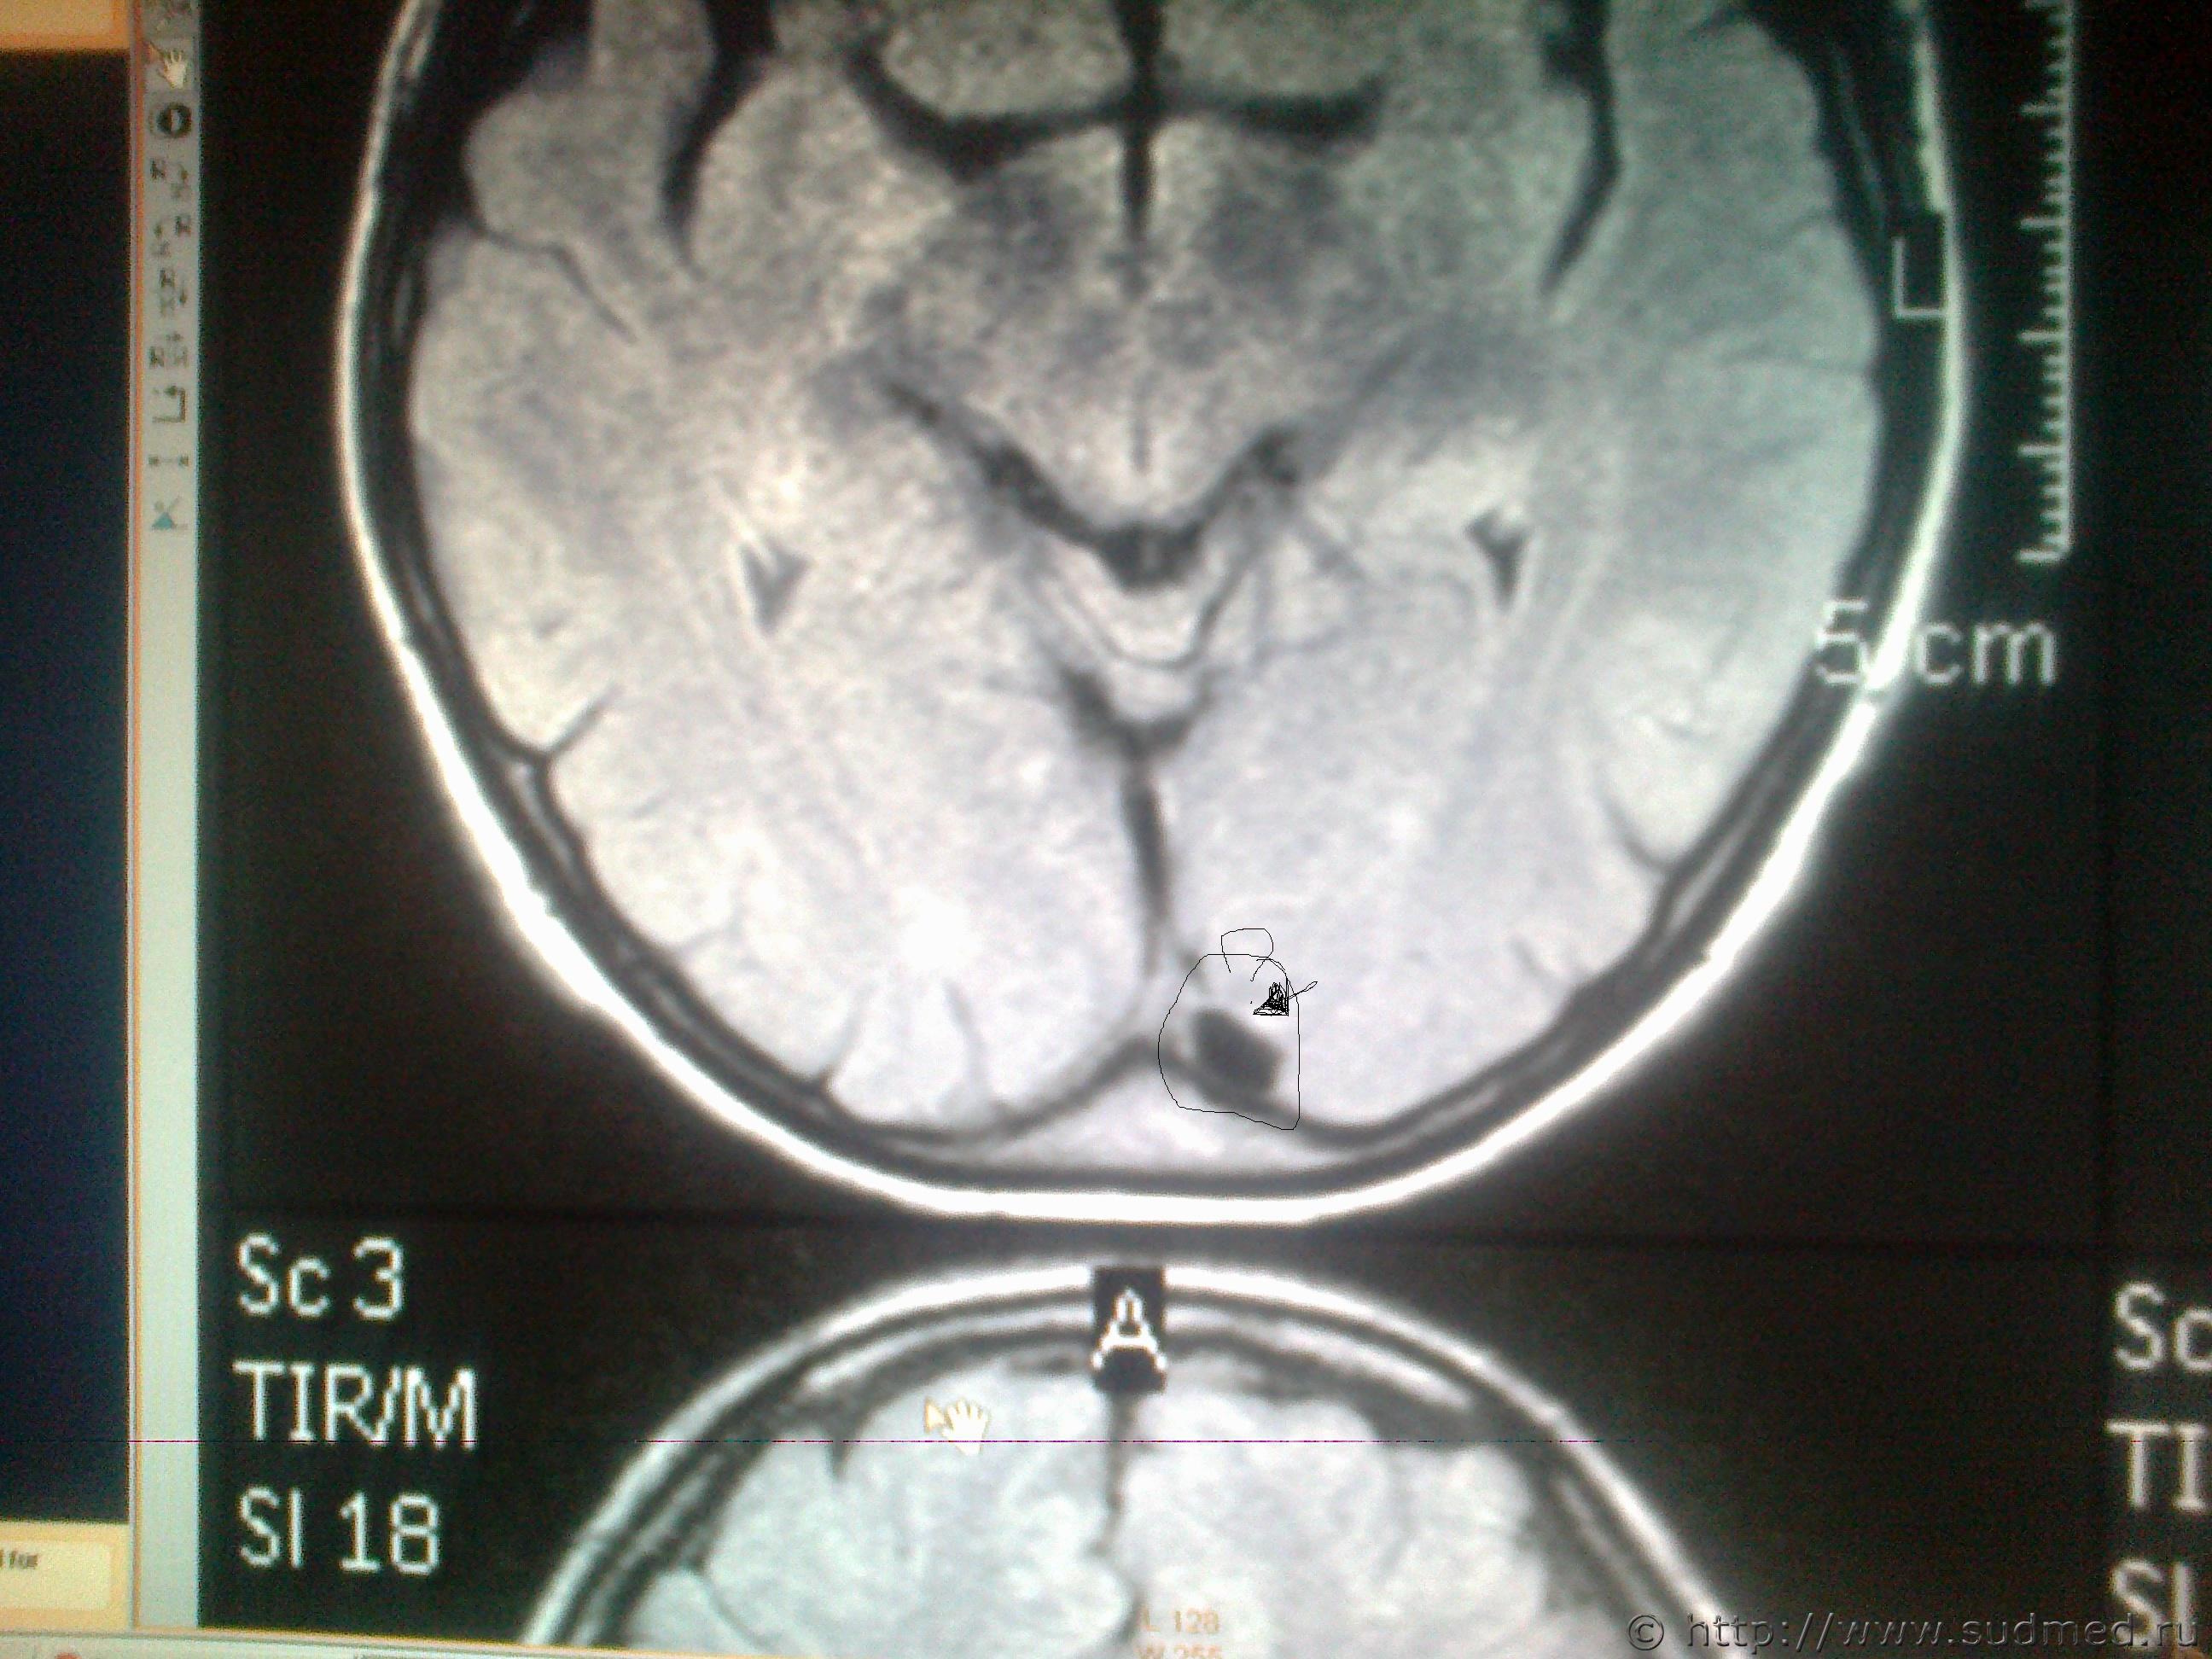

ув. специалисты! Мне оч. хочется узнать ваше мнение, что показано на мрт снимках в мозгу и на костной ткани, интересующие места обведены. Есть ли трещины на костях черепа или это шов и что значит чёрное- белое пятно на снимке мозга?

Светичок! Надо показать сами эти снимки специалисту по МРТ (на пленке и/или на электронном носителе. На эл.носителе даже лучше, т.к. на пленке могут быть распечатаны, к примеру, 30 сканов, а, фактически, их 150 было выполнено и все они могут быть представлены Вам на диске или на флешке). Присланное Вами хуже по качеству, чем снимки, которые есть фактически и, на этом форуме, насколько мне известно, нет врачей имеющих сертификат по специальности"Рентгенология" и дополнительную специальную подготовку по ядерно-магнито-резонансной томографии. Поищите какой-нибудь форум рентгенологов, вероятно, там смогут дать более компетентные комментарии. Насколько я разбираюсь в МРТ (немножко): на снимках №1, 2 и 3 - вероятнее всего, ликворная киста. Возможно, это вариант развития, возможно, след от давно регрессировавшей (прошедшей, рассосавшейся) гематомы. В любом случае, даже если это изменение имеет посттравматическое происхождение, то травма была давно (месяцы или годы назад), на что указывает отсутствие признаков внутричерепной гематомы, перифокального отека вещества головного мозга. Только по этим снимкам ни один специалист не сможет серьезно и аргументированно доказать, что это: 1.именно последствие травмы и ни что другое, 2.точно установить дату этой предполагаемой травмы. (Просьба не путать специалиста с шарлатаном, который, "все что угодно за ваши деньги" - в суде такое "заключение" окажется несостоятельным). На снимках №4 и 5 - шов между затылочной и теменными костями, №6 - каналы диплоэтических вен (вены, проходящие сквозь кости черепа. Они извитые, а перелом, в такой проекции выглядит как прямая линия, перпендикулярно и косо-перпендикулярно пересекающая кость свода черепа). МРТ - неоптимальный метод для оценки состояния костей свода черепа (МРТ - великолепный метод для оценки состояния мягких тканей). Гораздо лучше - обычная рентгенография костей свода черепа. Желательно,сделанная на современном цифровом рентгеновском аппарате. Желательно - полипозиционная (т.е. не только стандартные снимки в прямой и одной из боковых проекций, а, в данном случае - прямая проекция,правая и левая боковые проекции, контактная рентгенограмма затылочной кости и, возможно, снимок с выведением места предполагаемого перелома в краеобразующую зону. Тогда на 100% будет понятно,что это такое. Вероятно, на 100% будет понятно уже на стадии рентгенограмм в прямой и боковых проекциях. Грамотный рентгенолог знает все это лучше, чем я тут написал). Можно, конечно, сделать мультиспиральную компьютерную томографию /МСКТ/ в костном режиме с 3-D реформацией изображения,однако, лучевая нагрузка будет больше, а информативность - сопоставимая. Если в итоге найдется что-то похожее на посттраматические изменения, то нужно будет провести исследование всех рентгенограмм, которые выполнялись непосредственно после конкретной травмы, если когда-то до неё делались рентгенограммы, МРТ, КТ головы - их тоже. Это уже задача судебно-медицинской экспертизы. + будут учитываться данные медицинских карт и прочие документы о лечении после этой травмы, о состоянии здоровья до неё и т.п., т.к. перелом кости/костей свода черепа, внутричерепная гематома протекают с весьма выраженной клинической симптоматикой (от чего-то "легкого" и похожего на "сотрясение головного мозга" до тяжелых невропатологических проблем).